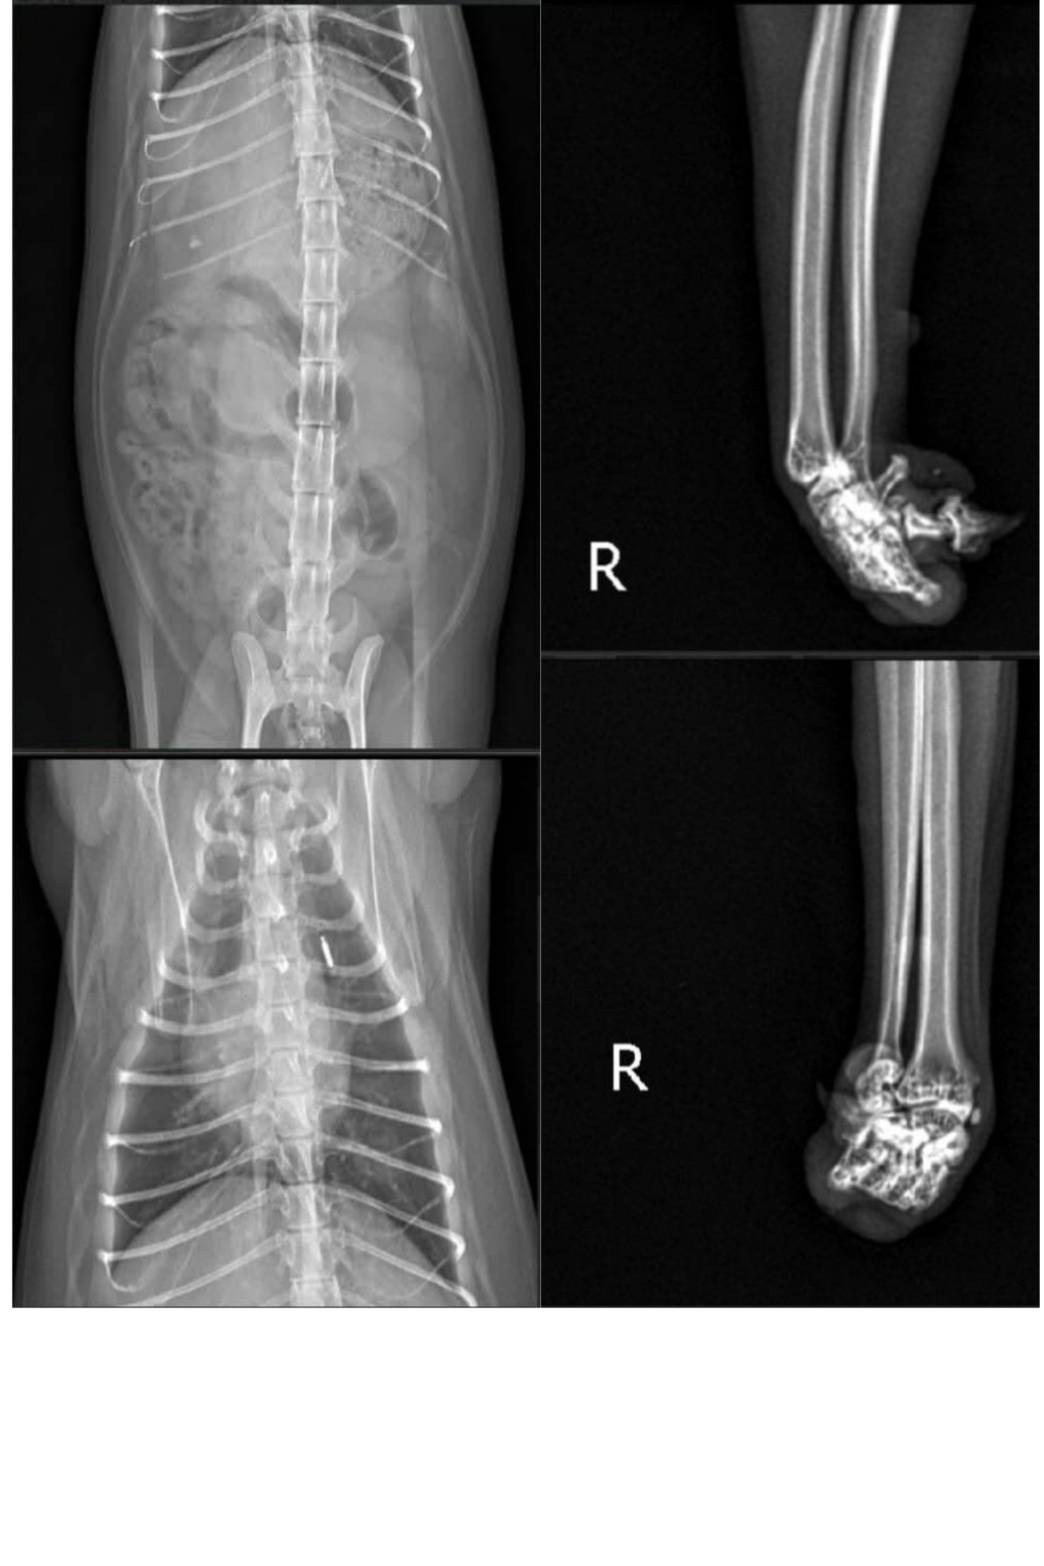

主題: 腳趾先天發育異常的Sabi 申請者姓名: TNR協會 花色: 玳瑁 申請日期: 2026-04-15 12:13:45 申請者部落格: https://www.facebook.com/SupportTNR/?locale=zh_TW 申請者臉書網址: https://www.facebook.com/SupportTNR/?locale=zh_TW 所在縣市/合作醫院: 台北市/沐恩動物醫院 治療費用: 10500元 需求名額: 35人 平均每單位: 300元 已報名名額: 12 尚需求名額: 23 報名人員: 1.SteveT x10 (已付款)

有晶片,身體很健康,血檢沒問題,腳有可能是先天發育異常,因為右後腳剛好也有一趾是沒發育完成的,其他身體的臟器,並沒看到有發育異常的問題。牙齒很好,沒貓愛滋/貓白血/心絲蟲,心臟快篩也是正常的,只是有跳蚤點了一錠除。